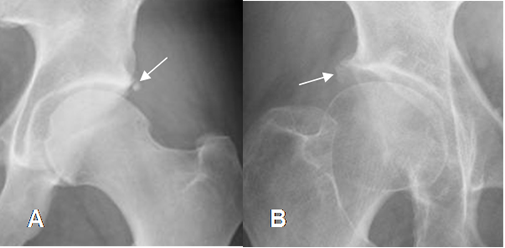

Fig 101. Pinzamiento tipo cam.

A y B: Rx AP de cadera. Prominencia en la parte externa de las cabezas femorales, en diferente grado, produciendo el signo de la empuñadura de pistola.